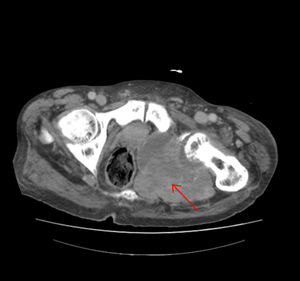

Presentamos el caso de un paciente varón de 82 años diagnosticado 10 años antes de enfermedad de Paget ósea con afectación poliostótica. Como otros antecedentes de interés presentaba fibrilación auricular e insuficiencia cardiaca crónica. Acudió a la unidad y consulta de atención inmediata (UCAI) por astenia, anorexia y edemas en las extremidades inferiores de 15 días de evolución. En la anamnesis por aparatos refería dolor en la región isquiopubiana izquierda desde hacía 6 meses, que había ido en aumento y que aparecía tanto en reposo como con el ejercicio. Se decidió ingreso en planta de hospitalización para tratamiento de la insuficiencia cardiaca y estudio del origen del dolor. En la exploración física presentaba palidez de piel y mucosas, auscultación cardiaca irregular con soplo sistólico aórtico, disminución generalizada del murmullo vesicular en la auscultación pulmonar, edema con fóvea hasta la raíz de ambos miembros inferiores y dolor a la movilización e impotencia funcional de articulación coxofemoral izquierda. En el tacto rectal no se encontraron masas y existían restos de heces normales. En la analítica destacaba hemoglobina de 9,5g/dl con volumen y hemoglobina corpuscular media normales, proteína C reactiva: 21,2mg/dl (0,2-0,8), fibrinógeno: 722mg/dl (200-400), velocidad de sedimentación glomerular: 120mm (1-15), fosfatasa alcalina: 155 U/l, hierro: 23,6μg/dl (50-150) transferrina: 155μg/dl (300-360), ferritina: 1.144μg/l (50-350), índice de saturación: 12% (20-40), receptor soluble de transferrina: 7,88μg/l (2-4); los marcadores tumorales eran normales. En la radiografía de tórax presentaba derrame pleural bilateral de escasa cuantía y lesiones compatibles con enfermedad de Paget en ambos hombros y el quinto arco costal izquierdo. La radiografía de pelvis mostró múltiples lesiones compatibles con enfermedad de Paget y una imagen lítica de mayor tamaño en isquion izquierdo (fig. 1). Se realizó una gammagrafía ósea que mostró imágenes compatibles con enfermedad de Paget y ausencia de captación en isquion izquierdo (fig. 2). Se solicitó una tomografía computarizada toraco-abdómino-pélvica que objetivó una gran masa de contornos lobulados con focos de calcificación que destruía el isquion y acetábulo izquierdo de 12 x 12 x 16cm (fig. 3). Ante la sospecha de neoplasia ósea sobre enfermedad de Paget se realizó una biopsia de hueso iliaco cuyo estudio fue compatible con un sarcoma pleomórfico indiferenciado de alto grado no osteogénico, vimentina positivo, con coexpresión de CD-68 y mínima expresión de actina y desmina. La evolución del paciente fue desfavorable, con gran afectación del estado general y dificultad para controlar el dolor, se decidió iniciar tratamiento con radioterapia para control fundamentalmente sintomático. Finalmente, el paciente falleció a la semana del diagnóstico anatomopatológico.